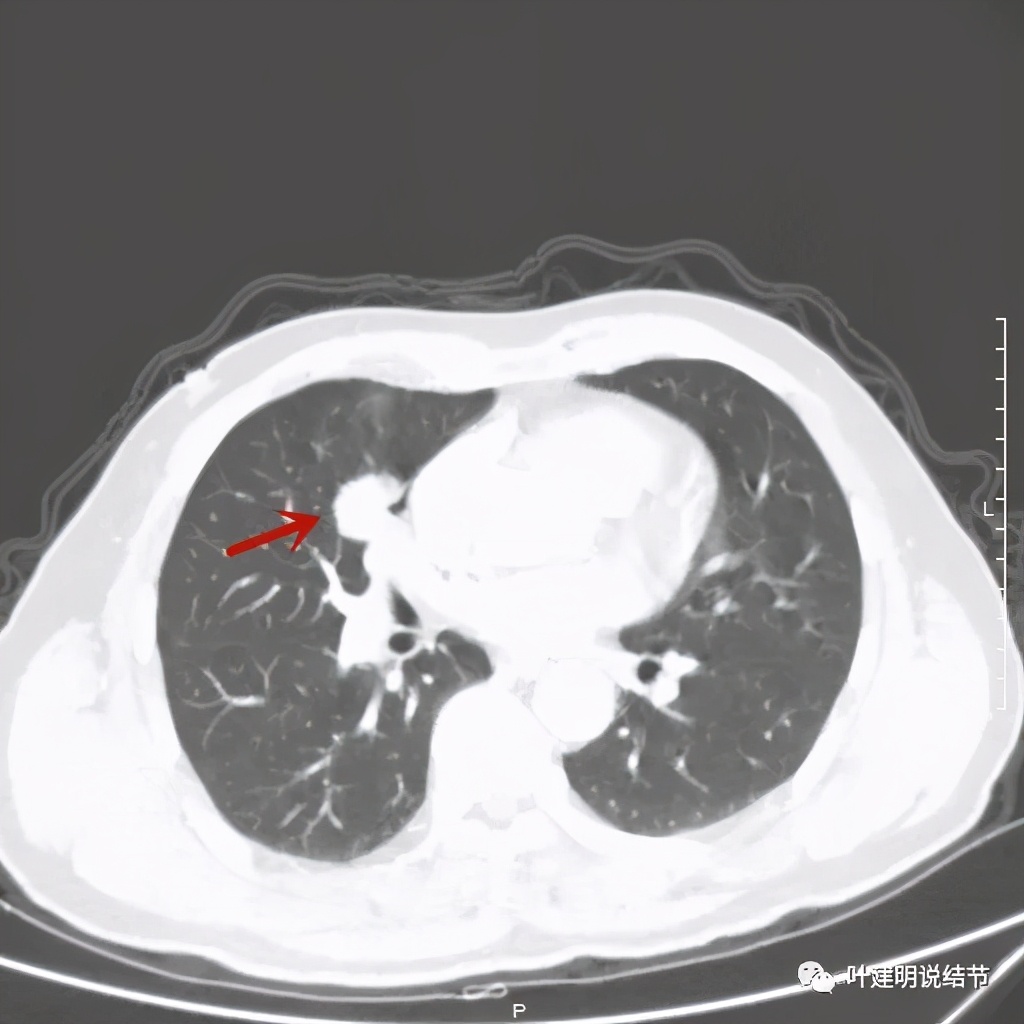

那么当时的胸部影像又是如何的呢?

病灶有分叶及胸膜牵拉

以上几图示病灶膨胀感明显,无卫星灶,周围无渗出性改变

纵隔窗分叶明显,密度不均

黄色箭头示病灶附近淋巴结或癌结节可能性大